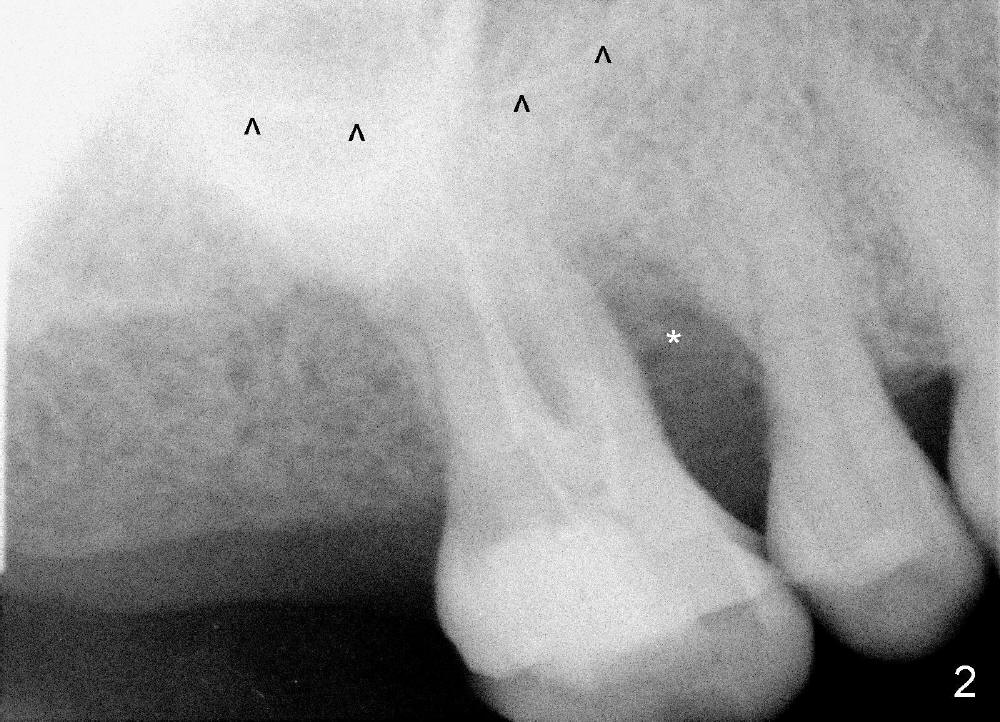

The upper right 1st molar fractures, the lingual portion mobile (Fig.1). There are deep pockets mesiolingually and distolingually. Fig.2 is preop PA, showing mesial bone resorption (*). The 84-year-old lady agrees extraction and immediate implant. Extraction is difficult due to not only root fracture but also hemorrhage. Following debridement of granulation tissue, the 3 sockets are packed with gauze for hemostasis. Even so, there is oozing from the bone. The septum can not be seen clearly. Its position is determined by an explorer. Osteotomes have to be used for osteotomy in the septum, followed by taps. The first intraop PA shows that 5x20 mm tap penetrates the sinus floor (Fig.3 ^). The osteotomy is further enlarged until 7x17 mm tap with stability (Fig.4). So far there has been no sign of sinus membrane perforation. Mixture of freeze dry mineralized bone and Osteogen is placed in the socket and pushed to the buccal and lingual walls as well as into sinus using a 4 mm flat end osteotome. A 7x17 mm implant is initially difficult to be inserted possibly due to blockage by bone graft. The osteotomy have to be recreated by a series of osteotomes and taps before placement of the 7x17 mm implant. It appears that the apical threads have been engaged into the sinus floor for primary stability (Fig.5). The insertion torque is 40 Ncm. According to our experience (1,2), this is not enough; finally the torque is increased to 60 Ncm by turning the implant more apically. The large implant obliterates the socket mesiodistally; the buccal and lingual gaps are filled with bone graft, followed by a collagen membrane (Fig.6 *) and suture. In order to protect the membrane, a short abutment is placed (A) and perio dressing (Fig.7*) is placed without occlusal interference. The abutment is removed 1 month postop, as the perio dressing has been dislodged. The patient returns for restoration 8 month postop. Bone regeneration occurs apparently in the coronal aspect of the implant (Fig.8), especially mesially (*, as compared to Fig.5). The gingiva-level implant is slightly subgingival mesially (Fig.9 M), probably due to high placement (compare to Fig.6). There is no bone resorption 6 months post crown (Fig.10 C) cementation.